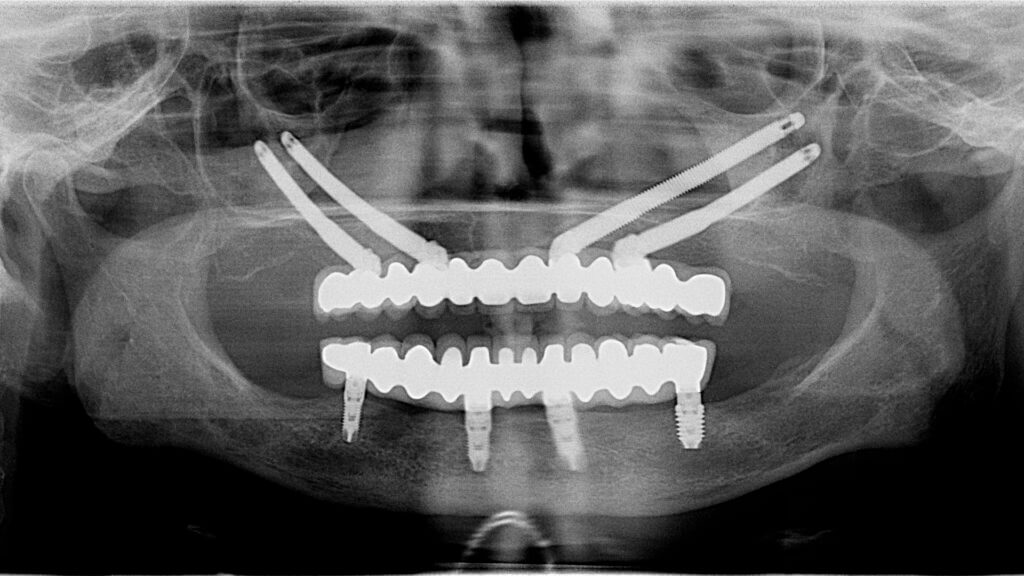

Ice cream, barbecues, seafood, cold milkshakes, crunchy salads, sandwiches… Summer tastes better when chewing doesn’t hurt. From 24-hour implants to periodontal treatments that save gums and teeth, we work with a clear goal in mind: chewing, talking or smiling doesn’t hurt. Because eating without discomfort should not be a luxury, but a necessity. Even more […]